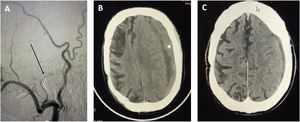

Por otro lado, Gelabert et al., quizá por desconocimiento de la literatura actual y a pesar de las referencias aportadas, expresan no compartir nuestra idea de que la embolización endovascular de la arteria meníngea media puede hacerse con sedación ligera. La embolización con Onyx es dolorosa y precisa de intubación orotraqueal en la mayoría de los casos14. No es así el caso de la embolización con polivinil-alcohol que puede realizarse en paciente despierto y cuya eficacia y seguridad han sido probadas anteriormente14,15. En nuestra práctica, también optamos por la eAMM mediante coil distal a la entrada de foramen espinoso, bajo sedación ligera (fig. 1). Esta maniobra nos permite obtener control proximal e impedir complicaciones derivadas de la oclusión de ramos que irrigan el cavum de Meckel y la rodilla del facial. Tras ello, la embolización controlada de ramas distales con polivinil-alcohol provee de estabilidad a largo plazo. Nuestra serie de 12 pacientes con 20 HSDC (pendiente publicación) mostró resolución del HSDC en todos los casos, no habiendo encontrado complicaciones tales como sangrado, infección, recidiva o deterioro visual. Es importante notar que las indicaciones en todos nuestros casos fue el fracaso del tratamiento quirúrgico y que en uno de nuestros pacientes el procedimiento tuvo que ser abortado al objetivarse un origen anómalo de la arteria oftálmica procedente de la arteria meníngea. Así pues, podemos confirmar que la eAMM es una terapia eficaz y probada en el manejo de HSDC resistentes a tratamiento quirúrgico o en pacientes con elevada comorbilidad y elevado riesgo anestésico2,9,10.

Caso tipo de paciente de edad avanzada con elevado índice de comorbilidad (índice Charlson>2, historia previa de infarto de arteria cerebral media) y riesgo anestésico. El paciente fue sometido a embolización con coils de arteria meníngea media y polivinil-alcohol de ramas distales (flecha, A). Tomografía preoperatoria tras fracaso del tratamiento quirúrgico mostrando hematoma subdural de 20mm, efecto masa y desplazamiento significativo de línea media (>5mm) (asterisco, B). Resultado tomográfico a las 4 semanas del tratamiento endovascular; muestra resolución completa del hematoma (C). El paciente fue capaz de resumir su actividad funcional previa al desarrollo del hematoma subdural crónico (escala modificada de Rankin 2).